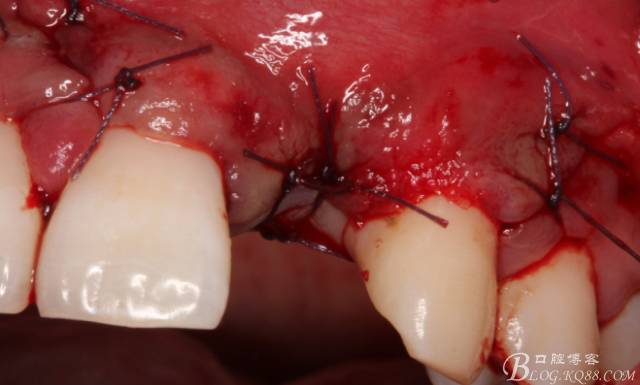

于是我果斷告知患者,手術(shù)失敗了,不能拖延,如不及時處理,炎癥繼續(xù)發(fā)展會很快波及鄰牙牙槽骨?;颊呓邮芪业慕ㄗh。切開翻瓣,骨粉及生物膜消失了,骨吸收嚴(yán)重,幸運的是,因為處理及時,鄰牙骨支持依然存在。

徹底掻刮。